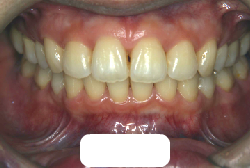

上顎前突

上顎前突(出っ歯)とは上顎が前に出ている状態です。この症状の特徴は、上下の歯並び全体の位置関係が相対的に上顎が優位になっていて、前歯が外に反っているだけでなく奥歯の位置関係も上が前にズレています。さらに凸凹の症状も合併していることがよくあり、上の前歯の見た目を気にして来院する方が多いのですが、実は今言った理由で噛み合わせにも異常があるため、このまま放置すると顎関節症という症状が出ることもあります。

「出っ歯を治したい」という主訴で来院したケースです。診断の結果、「2級1類の上顎前突+軽度叢生」と判明しました。2級というのは、基本的に出っ歯の噛み合わせになっていることを言います。その中でも上の前歯が著しく外に反っているケースを、「1類」といいます。初診時の横向きの写真を見ると、それがはっきり分かります。上の前歯に押されて唇も膨らんで、審美線をかなりオーバーしています(審美線とは、鼻の先端と顎の先端を結ぶ線のことで、この線よりも唇は内側にある方が良いとされています)。

このような症状の場合は、前歯を内側に入れるためにかなり大量の隙間を必要とします。通常は上下左右の小臼歯を抜歯させていただくのが正解です。治療後は歯の角度が正しくなっただけでなく、唇の審美性が大幅に改善しました。もちろん噛み合わせ的にも正しい状態が確立しています。